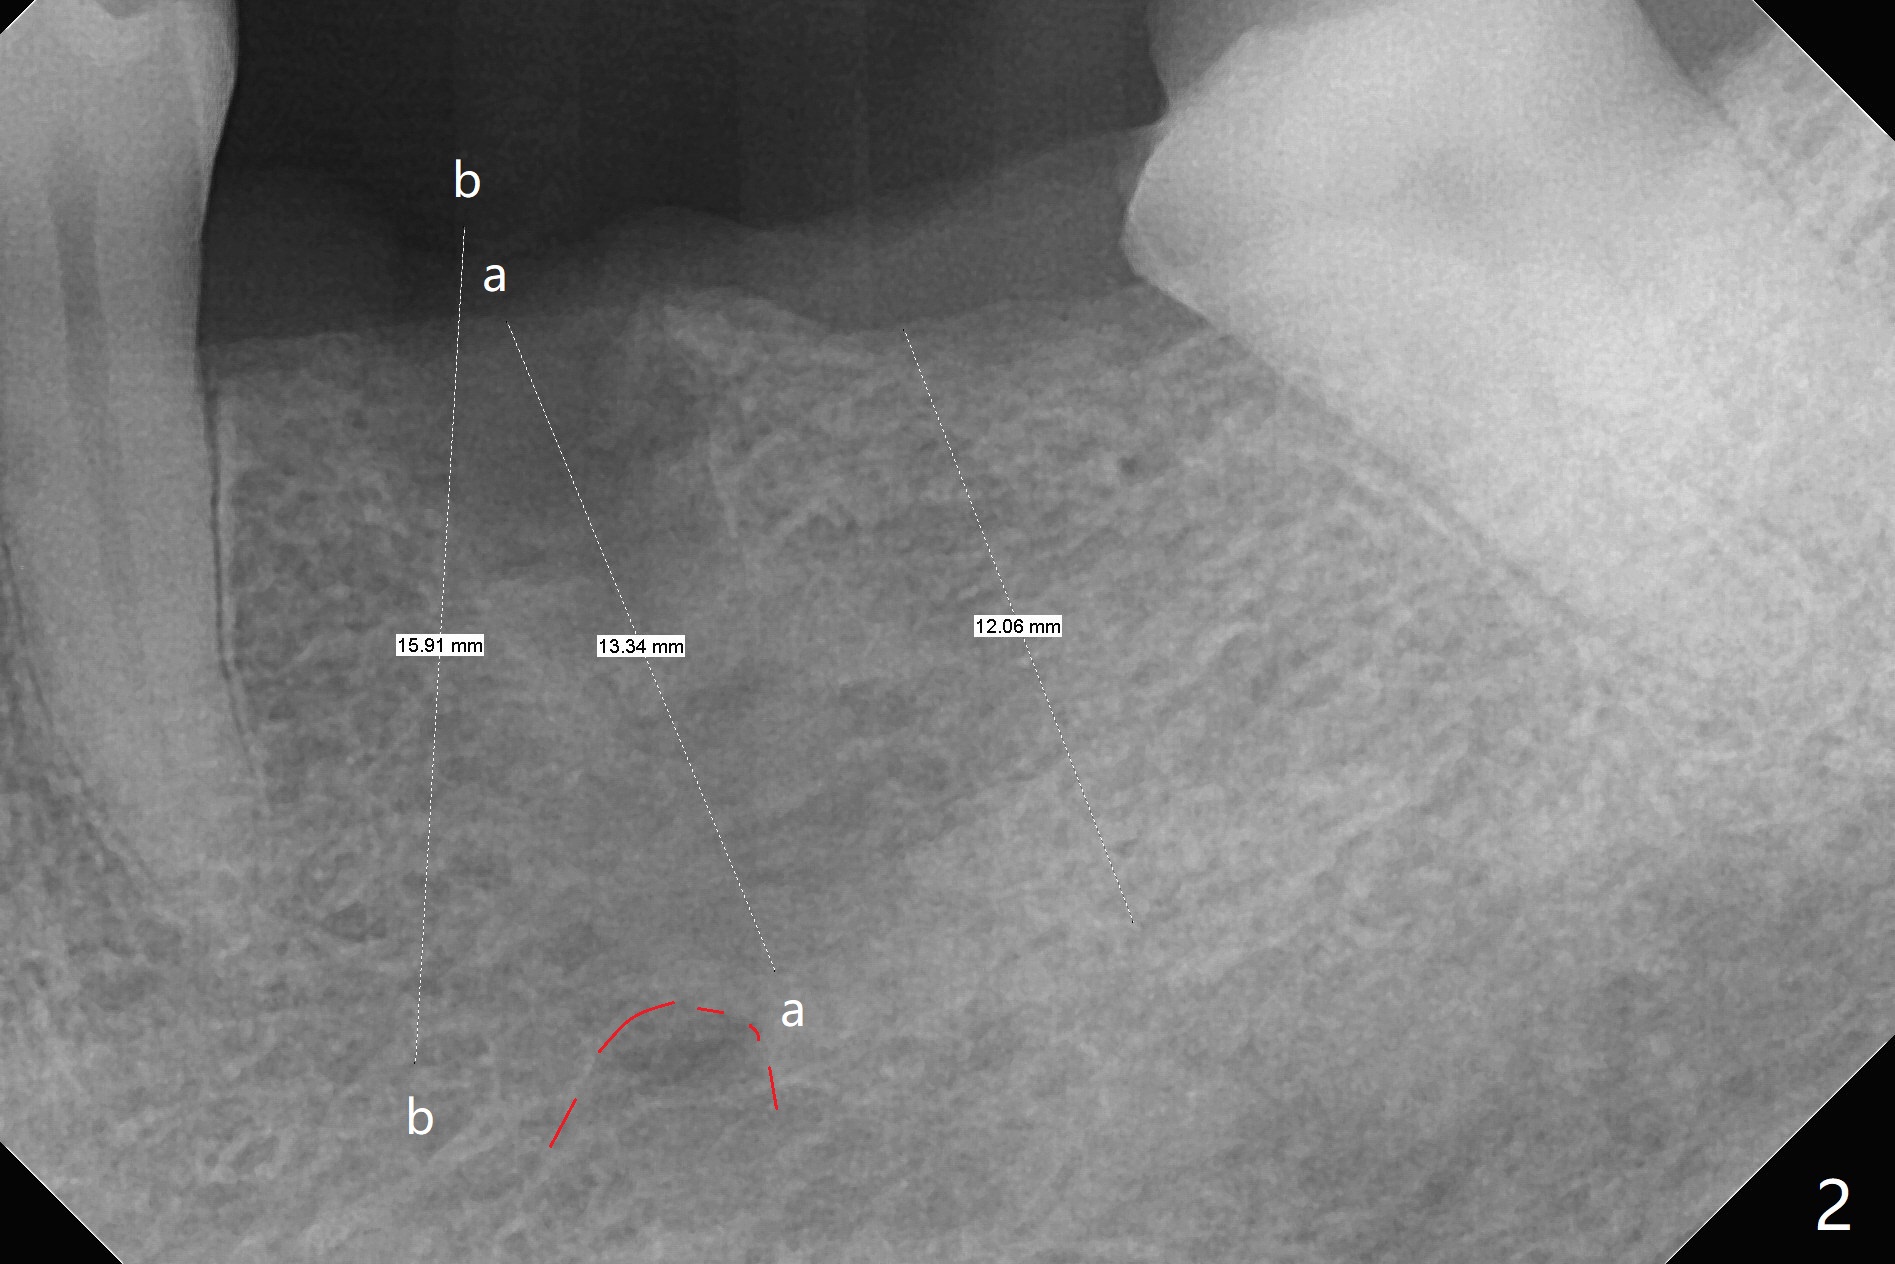

When the tooth #20 is extracted, the buccal and lingual plates are intact, but the apical lesion is deep. A PA is taken (Fig.1). Osteotomy will be established either along the long axis of the original socket (Fig.2 a line) or in the mesial slope (b line). Either osteotomy may damage the Mental Loop (red dashed line). To reduce the complication, osteotomy is being made by inserting 3.8 to 6 mm taps. In fact the 6 mm tap achieves stability (Fig.3,4), but it invades the buccal gap. When the tap is removed, the bottom of the socket is sensitive to probing with oozing from the socket. To reduce further compromise of the buccal space, Lindamann bur is used to remove the bone from the lingual and mesial plate, followed by placing a 6x17 mm implant with >50 Ncm (Fig.5). In fact the implant is placed shallower than the tap. When a 4x17 mm implant is placed at #19, there seems to be clearance from the Inferior Alveolar Canal (Fig.6). Postop there is no paresthesia. The buccal gap is <1 mm, which is filled with Vanilla Graft. After recementing the retainer (crown, C in Fig.7) at #18, periodontal dressing is applied to the sites of #19 and 20. Impression is taken 4 months postop with that of #15.